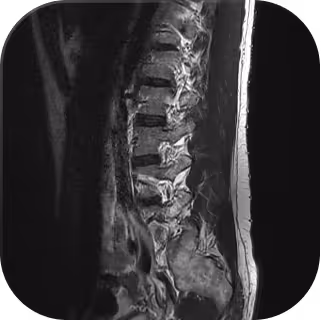

Our Whole Body MRI & CT Chest detects silent risks before symptoms appear. Check for cancer, tumours, aneurysms, cysts and organ disease with a single scan.

Each MRI is analysed by specialist radiologists and Everlab physicians, transforming complex imaging into clear, personalised health insights.

Whole-Body MRI

Advanced full body MRI & CT chest imaging with personalised insights from world class doctors, all tailored to your medical profile.